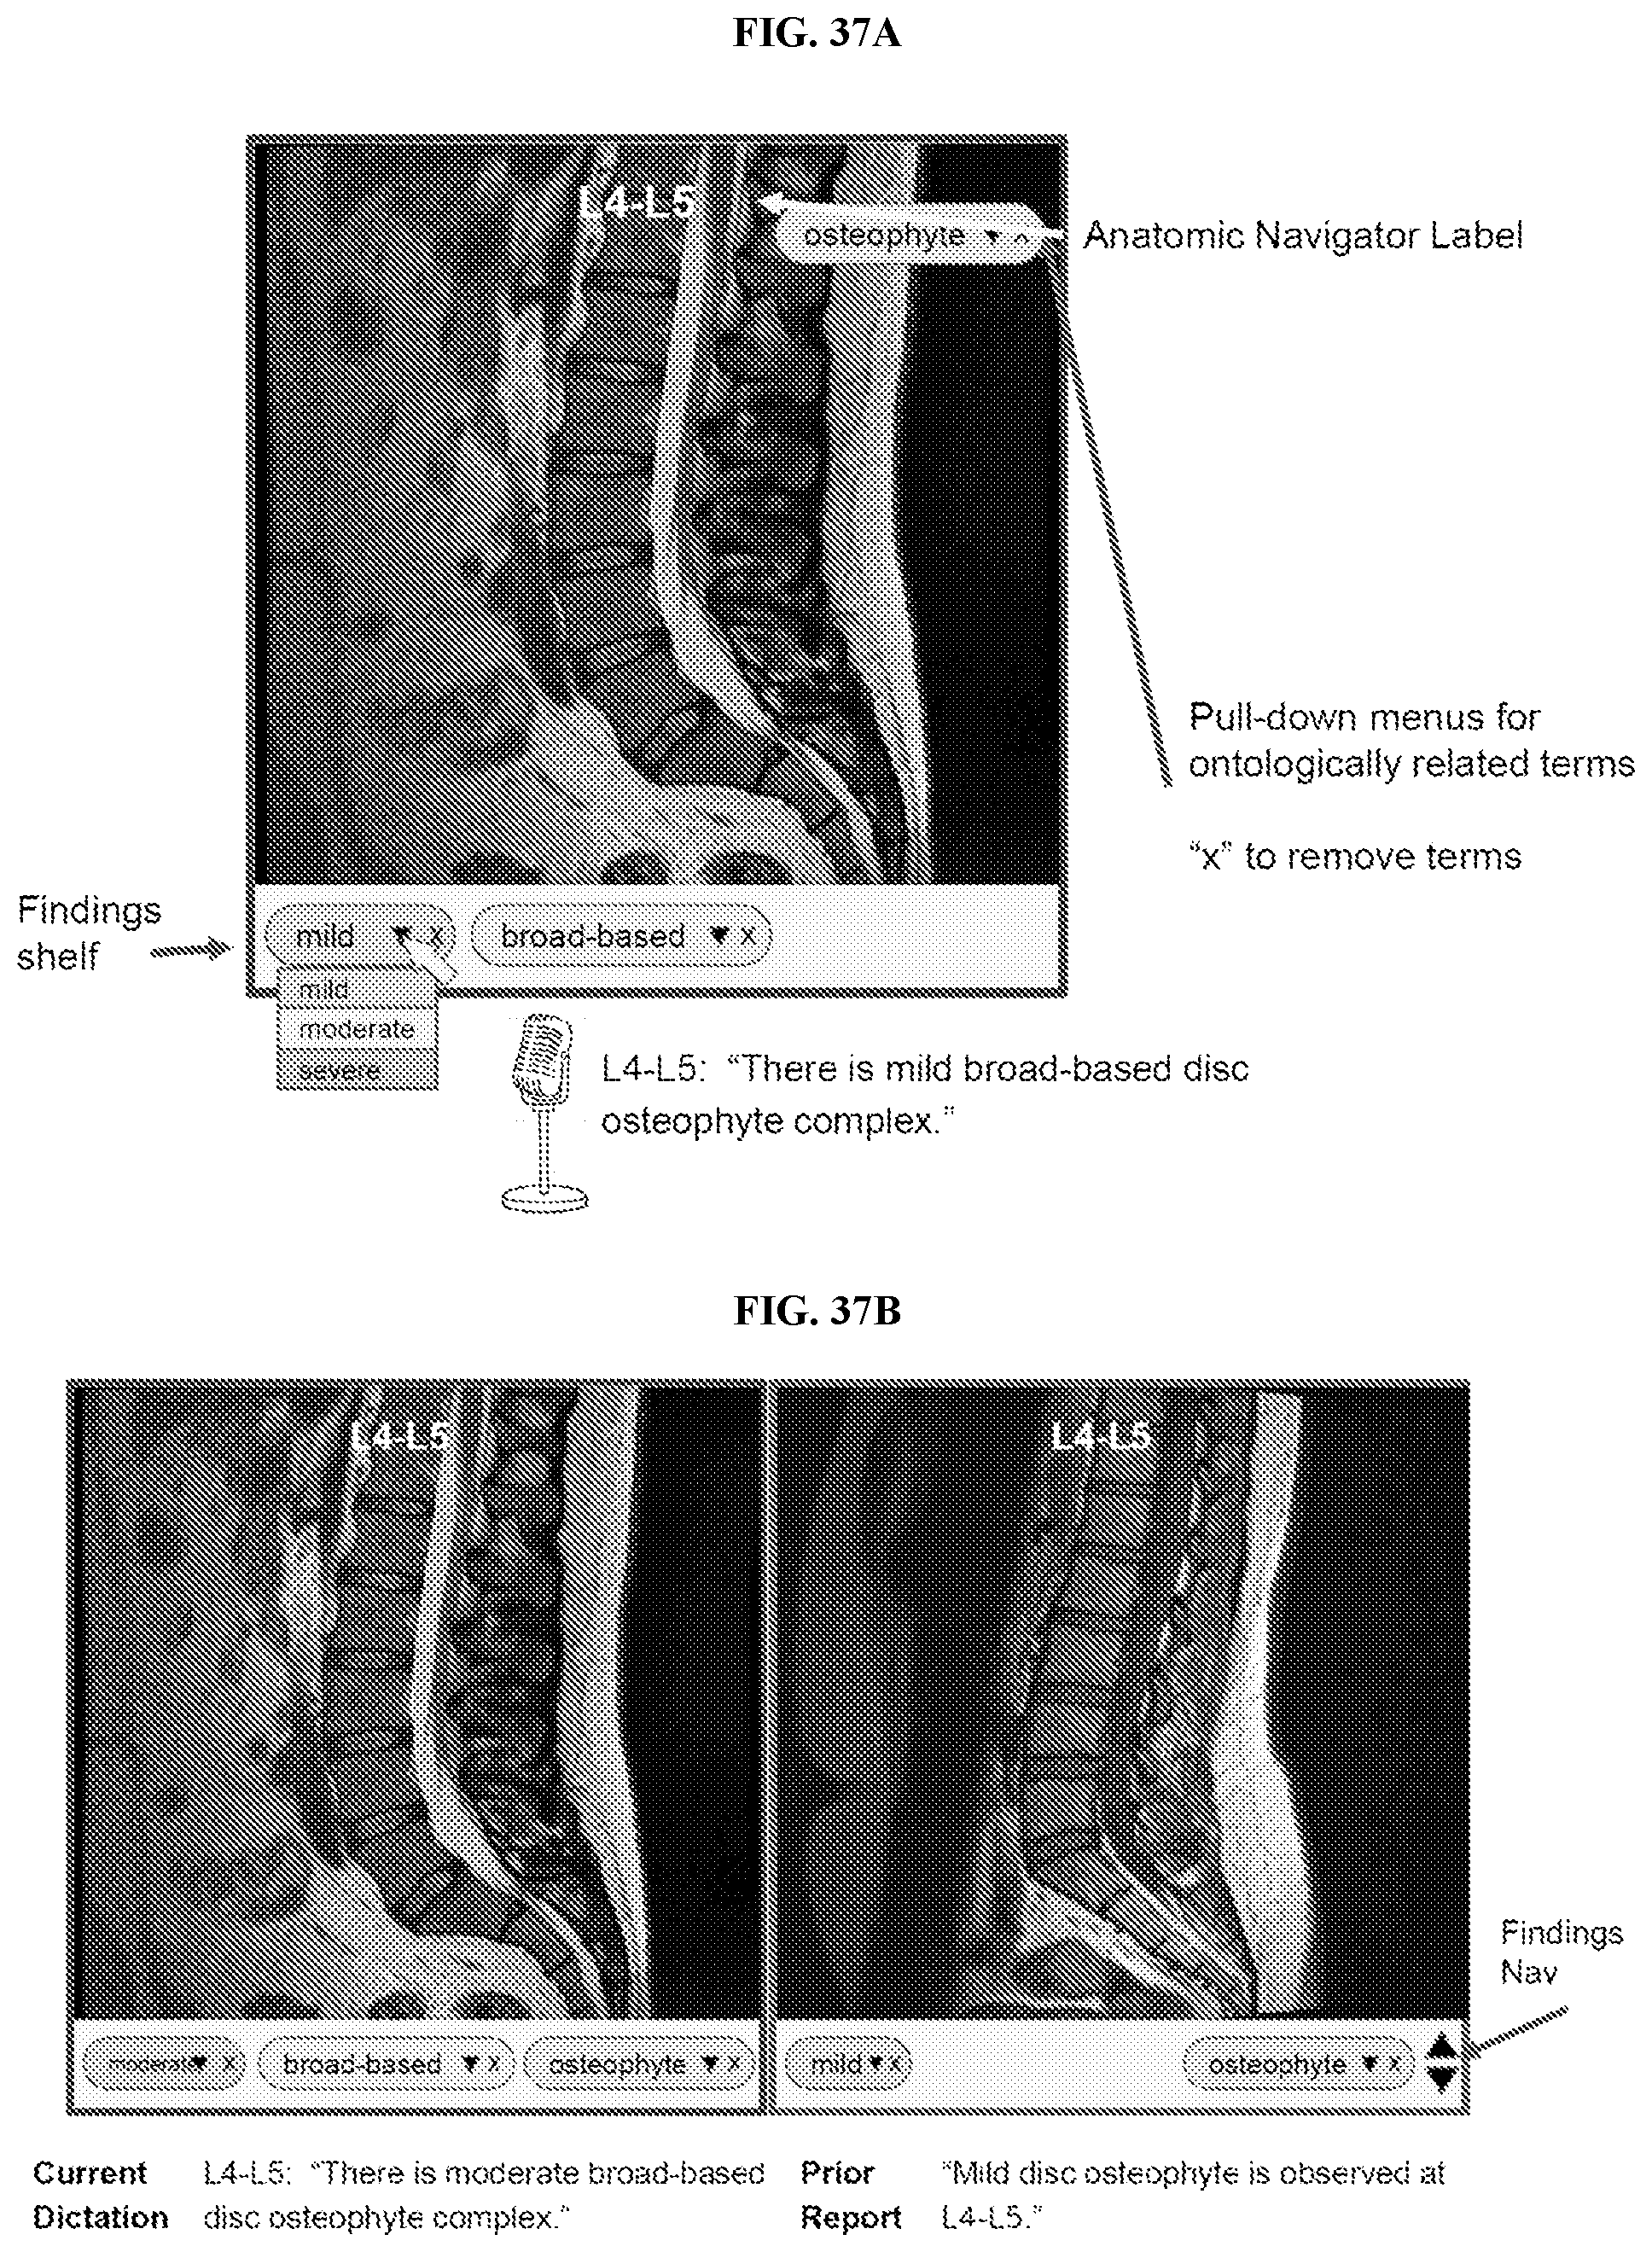

Disclosed herein are systems, methods, and software for providing a platform for artificial intelligence-assisted image analysis.

1.-88. (canceled) 89. A computer-based system for displaying a medical report, comprising:

(a) a processor; (b) a display; (c) a non-transitory computer readable storage medium encoded with a computer program that causes said processor to:

display a medical image on said display, wherein said medical image comprises an anatomic structure; generate a link corresponding to said anatomic structure; and display said medical report comprising said link, wherein said selection of said link retrieves said medical image for viewing. 90. The system of 91. The system of 92. The system of 93. The system of 94. The system of 95. The system of 96. The system of 97. The system of 98. The system of 99. The system of 100. The system of 101. The system of 102. The system of 103. The system of 104. The system of 105. The system of 106. The system of 107. The system of generate said link corresponding to said coordinate of said medical image. 108. The system of 109. The system of